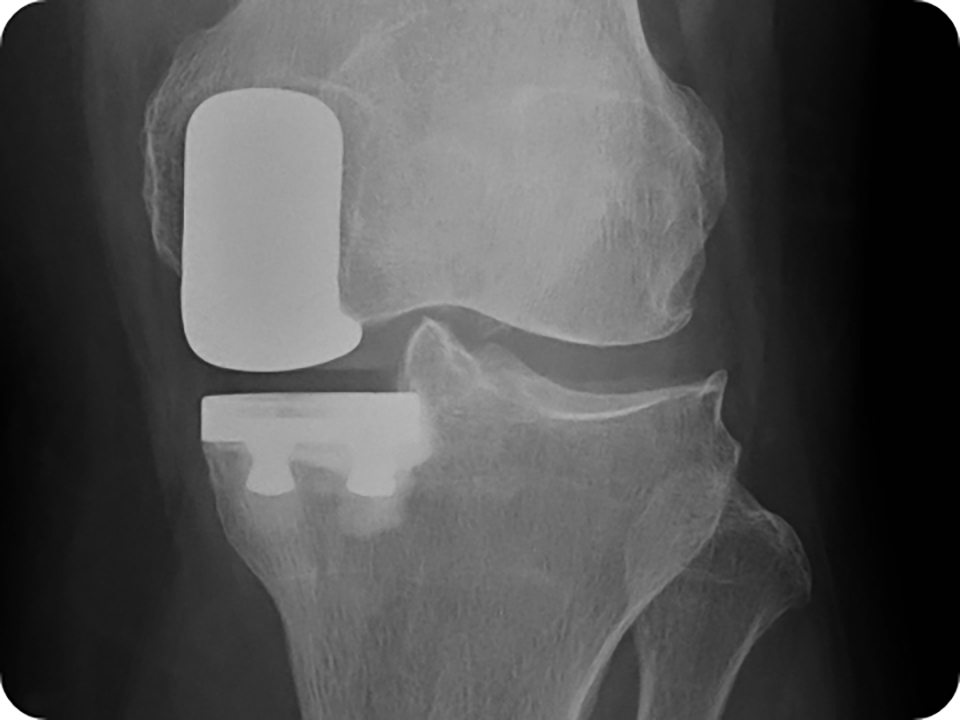

まれに、膝関節置換術後に感染症を発症する場合があります。感染症は、切開部位または膝関節置換コンポーネントの周囲で発生する可能性があります。

細菌が金属インプラントに付着する可能性があります。したがって、免疫系は膝関節置換術の金属コンポーネントの周囲の細菌を攻撃することが困難になります。